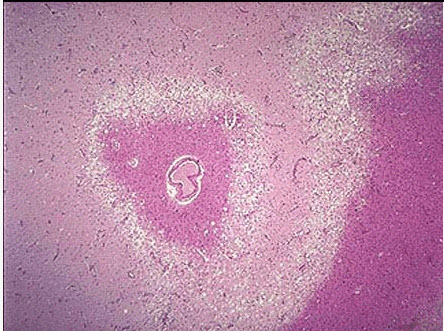

264、单项选择题

一孕妇,因胎盘早期剥离,失血性休克而突然死亡。尸解见一侧肾脏皮质区锥形灰白病灶,境界清楚。周边肾实质大面积出血,红褐色。

巨检如图,镜检如图所示,可作出何种病理诊断()

A.肾出血性梗死

B.肾贫血性梗死

C.肾脓肿

D.肾结核

E.慢性肾小球肾炎